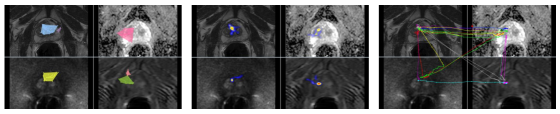

As a proof-of-concept, we tested C-CAD on a multi-screen prostate MR screening experiment. Promising results show the flexibility and generalizability of our algorithm in dealing with more complex tasks including more than one screen.

This experiment was performed on a multi-parametric MRI scan of a single subject. MRI characteristics are: axial T2 weighted (T2w), with FOV of and resolution of , Dynamic Contrast Enhanced (DCE) with FOV of and resolution of , , Diffusion Weighted Imaging (DWI) with FOV of and resolution of . Apparent Diffusion Coefficient (ADC) map was derived from 5 evenly spaced b value () DWI.

One of our participating radiologists, an expert in prostate cancer screening, examined multi-parametric MRI (four 3D images) for routine prostate cancer screening. Based on the results reported in Fig. 16, it is evident by the sparsified graphs that the radiologist used axial T2-weighted images (anatomical information) and ADC maps (showing magnitude of diffusion) more frequently than other two images. This observation suggests that although all four modalities are being used for making a diagnostic decision T2-weighted and ADC map are more informative to the radiologists in the screening process. This observation can be useful in further developments of automatic computer-aided diagnosis systems.

Quantitative results of our method for different modalities as well as the variation over these modalities are shown in Fig. 16 and Fig. 17, respectively. In screening, DWI and DCE modalities were used less frequently than T2-weighted and ADC modalities; therefore, the initial graph representations of the DWI and DCE are less dense compared to those of T2-weighted and ADC. For those less dense graphs, the sparsification algorithm achieved a similar MSE performance in most edge ratios larger than 0.5. From the reason that the sparsification algorithm keeps the graph in a of the original graph, we cannot remove large number of edges from less dense graphs. This situation is reflected in diameter ratio and betweenness metrics.

As can be interpreted from the lung screening experiment, the less experienced participant had more crowded visual search patterns and examined the most lung volume. Also, from the prostate cancer screening experiment, we observed that radiologists use anatomical/structural information more frequently than other modalities in screening (i.e., diffusion MRI). This potentially shows the importance of anatomical information in prostate cancer detection but at the same time we noticed that when anatomical information gives less clues to radiologists about potential abnormality, radiologists looks for complementary information from other imaging modalities to make inference. Our system provides visualization of this process for the first time in the literature. Scanpaths across different screens prove this observation as can be seen in Fig. 16.